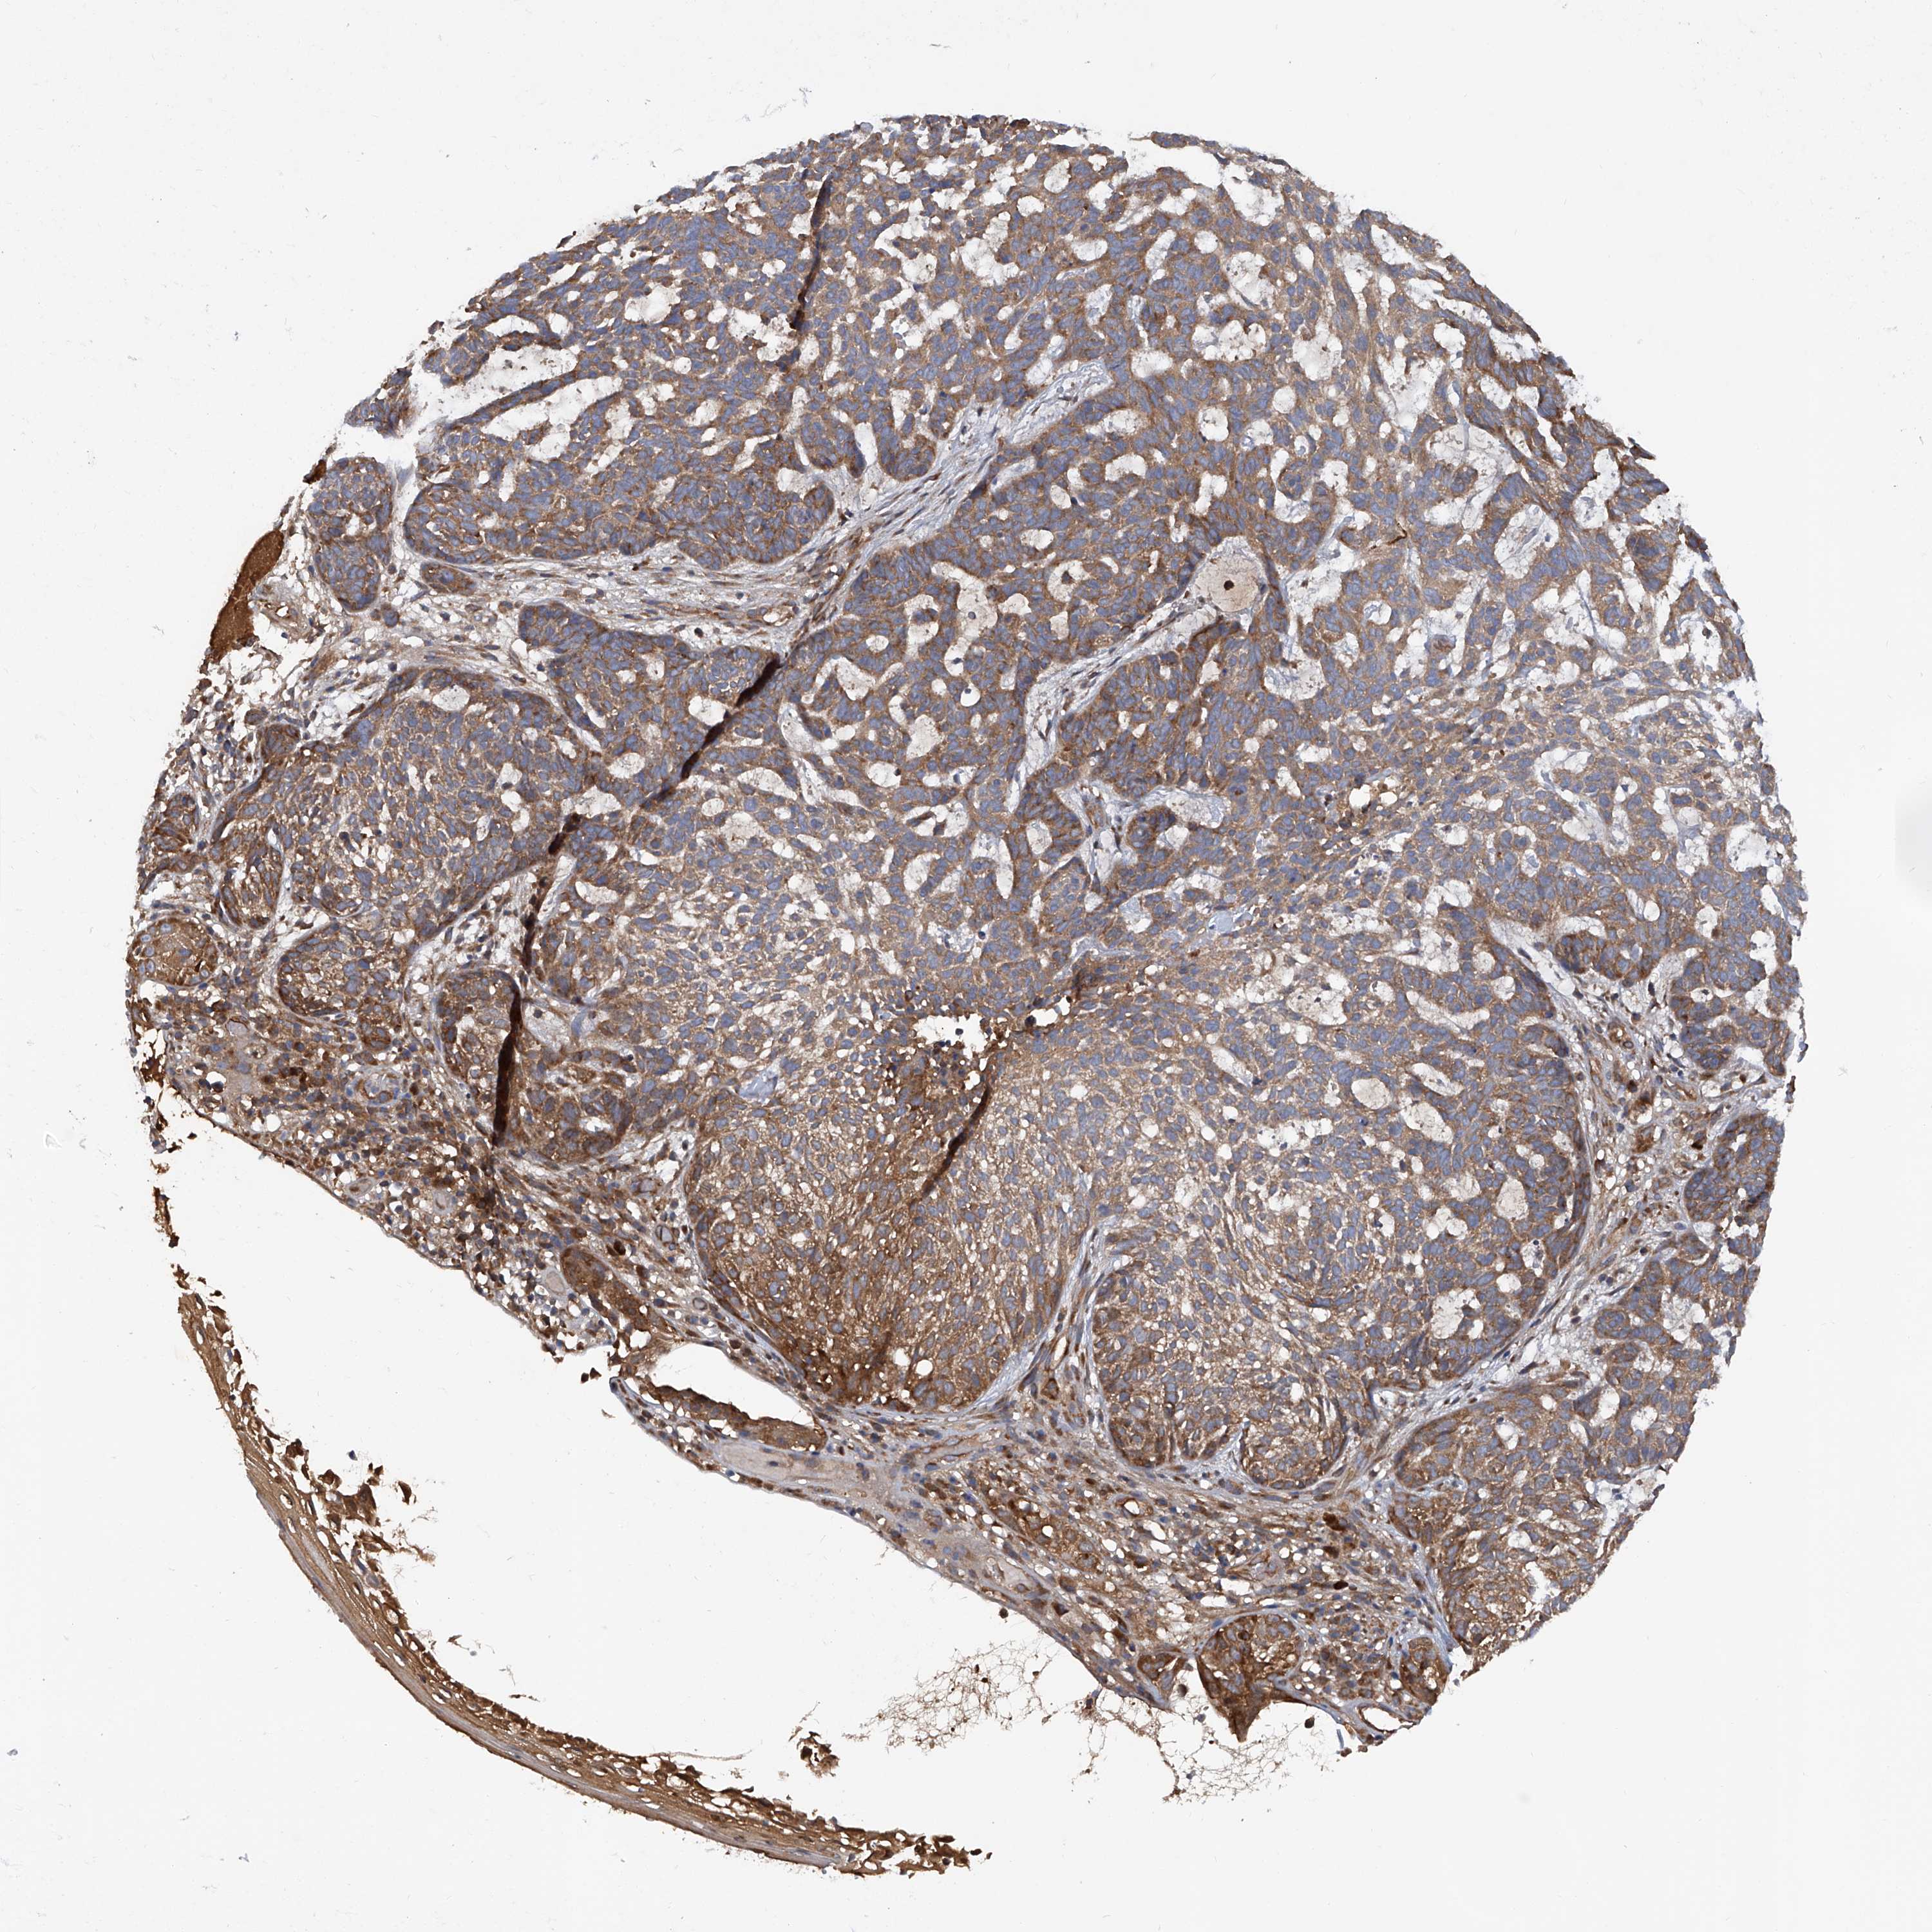

SKIN CANCER - Protein expressioni

A mouse-over function shows sample information and annotation data. Click on an image to view it in a full screen mode. Samples can be filtered based on level of antibody staining by selecting one or several of the following categories: high, medium, low and not detected. The assay and annotation is described here.

Each image is clickable and will lead to virtual microscopy that enables deeper exploration of all samples and also displays staining intensity scores, fraction scores and subcellular localization as well as patient and tissue information for each sample.

Antibody HPA031608

Staining

High

Medium

Low

Not detected

Intensity

Strong

Moderate

Weak

Negative

Quantity

>75%

75%-25%

<25%

None

Location

Nuclear

Cytoplasmic/membranous

Cytoplasmic/membranous,nuclear

Basal cell carcinoma